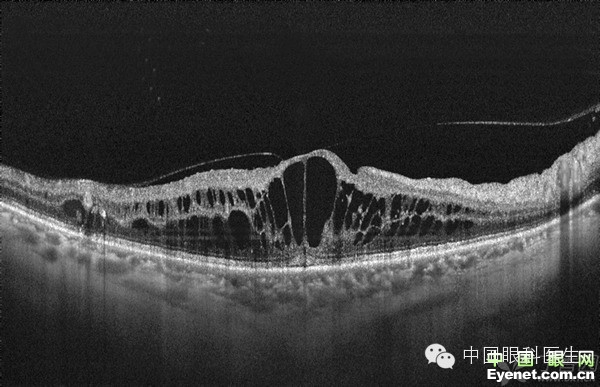

当糖网影响到黄斑区时会出现糖尿病黄斑病变的称呼:

1.水肿是否影响到黄斑中心凹分为--中心或非中心的

2.水肿扩散区域的大小状态---局限性或者弥散性

3.黄斑周边的毛细血管状态---缺血性或者非缺血性

4. 混合型--以上各种现象均存在